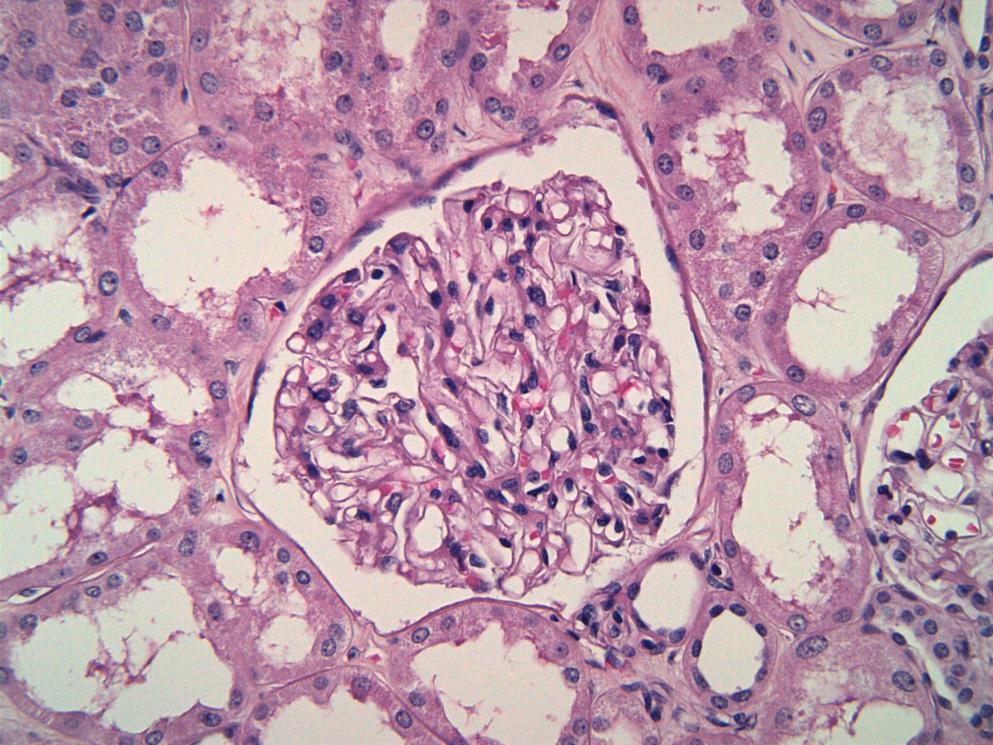

Complement-mediated kidney diseases (CMKDs) are chronic and progressive diseases in which dysregulation of the complement cascade causes or plays a key role in their pathophysiology1-3. CMKDs include C3 glomerulopathy (C3G), atypical hemolytic uremic syndrome (aHUS) 3,4, IgA nephropathy (IgAN), membranous nephropathy (MN) and immune-complex membranoproliferative glomerulonephritis (IC-MPGN)2-5.